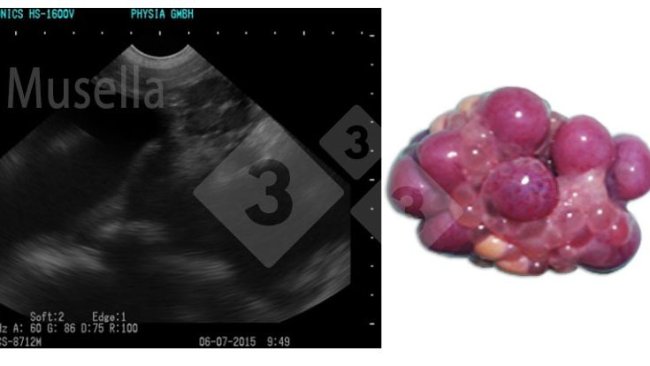

Respecto a las nuevas técnicas con ecógrafos de alta definición, que son capaces de identificar el estadio del ciclo de la cerda (pudiendo realizarse la inseminación poco antes o sobre la ovulación), científicamente son métodos de gran valor, pero con una importante necesidad de cualificación de la persona que la realiza y un alto nivel de disponibilidad del personal, ya que el seguimiento del crecimiento folicular, y por lo tanto del momento del ciclo estral, necesita de varias observaciones cada día, lo que dificulta su implementación a pie de granja.